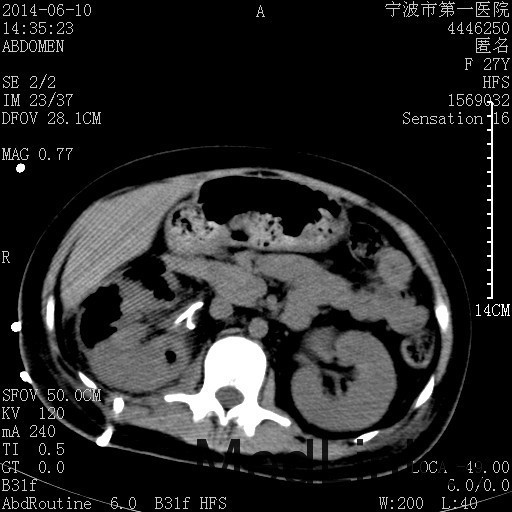

诊断为“气性肾盂肾炎,感染性休克,糖尿病酮症酸中毒” 血、尿、脓液培养均示“克雷伯杆菌” 入院第2天行“右双J管置入术” 入院第3天、7天行“右肾穿刺造瘘术” 入院1月行“右肾切除术” 术后顺利康复出院。

气性肾盂肾炎 • 气性肾盂肾炎是产气尿路病原体引起的急性肾实质坏死和肾周感染 • 大肠杆菌是最常见的病原菌,其次是克雷伯杆菌和变形杆菌 • 绝大多数气性肾盂肾炎患者合并糖尿病 • 死亡率19%至43%,单独的内科治疗通常是致命的,大部分患者最终需要行肾切除术 下一步治疗方案 • 拟行右肾切除术 • 患者经充分引流、抗感染治疗后现病情平稳,血糖控制良好 • 感染灶范围大,不能通过保守治疗消除,以往经验告诉我们保守治疗效果往往不佳 • 长期抗生素应用易引起真菌感染、伪膜性肠炎等并发症 • 若细菌对泰能耐药,后续抗感染治疗将十分困难 术前评估 • 手术风险评估(NNIS分级 2~3分) – IV 类手术切口(1分) – P3有严重系统性疾病,日常活动受限,但未丧失工作能力(1分) – T1手术在3小时内完成(0~1分) – 营养危险评分(NRS-2002) 营养状态评分3分+疾病严重程度评分2分=5分 围手术期治疗 • 术前、术中、术后血糖控制和调整 • 术后重症监护支持 • 感染控制和抗生素使用 • 手术前麻醉准备 患者最终在入院后1月行右肾切除术,术后康复出院。